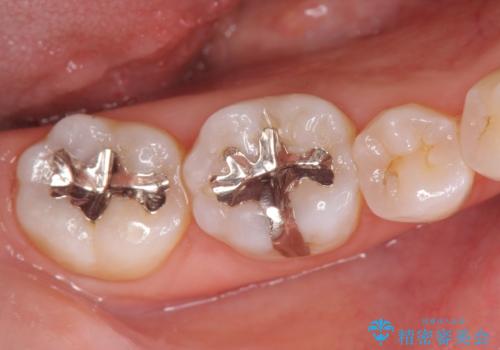

- 笑った時に見える銀歯を外したいと希望され来院されました。

銀歯の下には初期の虫歯も見られたので、除去後精密なシリコン印象を行いセラミックインレーを製作しました。